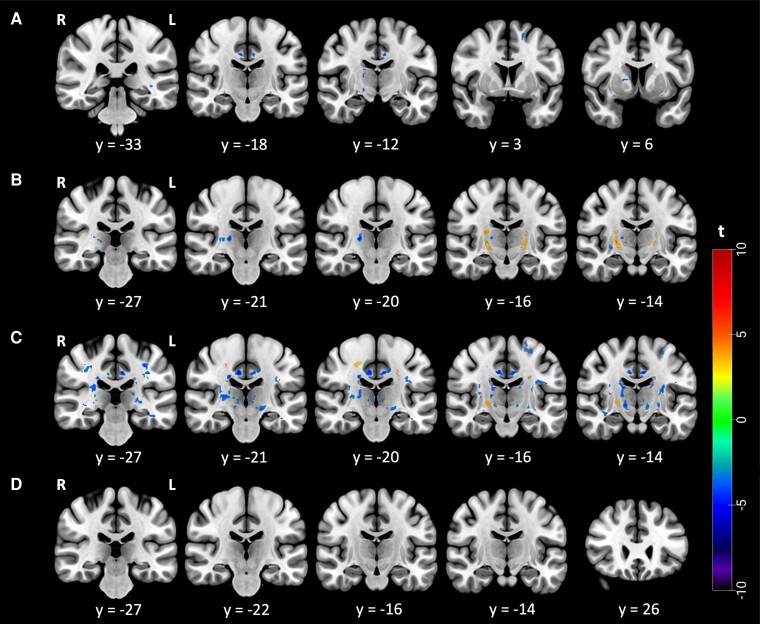

Amyotrophic lateral sclerosis, a progressive neurodegenerative disease, presents challenges in predicting individual disease trajectories due to its heterogeneous nature. This study explores the application of texture analysis on T1-weighted MRI in patients with amyotrophic lateral sclerosis, stratified by the D50 disease progression model. The D50 model, which offers a more nuanced representation of disease progression than traditional linear metrics, calculates the sigmoidal curve of functional decline and provides independent quantifications of disease aggressiveness and accumulation. In this research, a representative cohort of 116 patients with amyotrophic lateral sclerosis was studied using the D50 model and texture analysis on MRI images. Texture analysis, a technique used for quantifying voxel intensity patterns in MRI images, was employed to discern alterations in brain tissue associated with amyotrophic lateral sclerosis. This study examined alterations of the texture feature autocorrelation across sub-groups of patients based on disease accumulation, aggressiveness and the first site of onset, as well as in direct regressions with accumulation/aggressiveness. The findings revealed distinct patterns of the texture-derived autocorrelation in grey and white matter, increase in bilateral corticospinal tract, right hippocampus and left temporal pole as well as widespread decrease within motor and extra-motor brain regions, of patients stratified based on their disease accumulation. Autocorrelation alterations in grey and white matter, in clusters within the left cingulate gyrus white matter, brainstem, left cerebellar tonsil grey matter and right inferior fronto-occipital fasciculus, were also negatively associated with disease accumulation in regression analysis. Otherwise, disease aggressiveness correlated with only two small clusters, within the right superior temporal gyrus and right posterior division of the cingulate gyrus white matter. The findings suggest that texture analysis could serve as a potential biomarker for disease stage in amyotrophic lateral sclerosis, with potential for quick assessment based on using T1-weighted images.